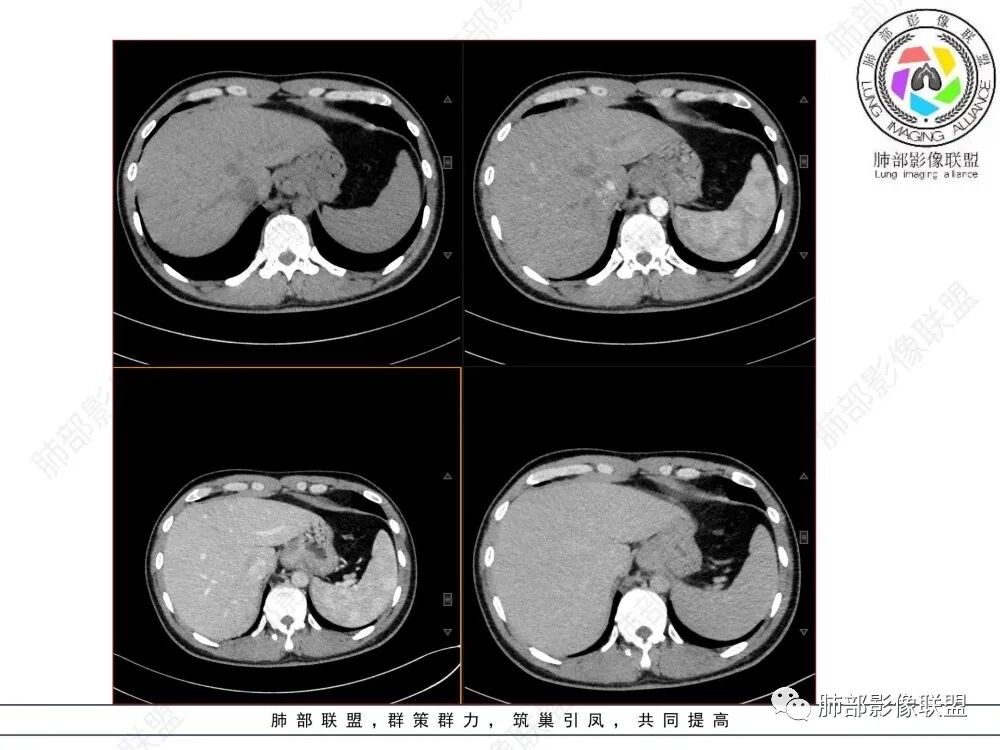

影像学特点:类纵隔区病变,沿食管生长,形态不规则,但边界清楚,内部信号/密度均匀,强化程度比较弱。

影像诊断思路:起源食管肿瘤(非黏膜起源,肌层起源),良性或低度恶性肿瘤可能性大,一般以神经鞘瘤、胃肠间质瘤及平滑肌瘤为主。食管神经鞘瘤强化明显均匀、以食管上段多见,周围常见炎性增大淋巴结,不太符合;胃肠间质瘤小的比较均匀,大的不均匀,但强化程度较高;影像上看这例病例比较符合平滑肌瘤。

造影虽然像外压,但是ct肯定更清楚,看ct就是一个环绕管壁生长,管腔狭窄,定位应该没有问题,但是大家病理都答对了,太厉害了

T2低信号是关键,提示平滑肌细胞

食管平滑肌瘤是最常见的食管良性肿瘤,多见于男性,男女之比为2.6:1,高发年龄 30~60岁之间与食管癌相比,食管平滑肌瘤 的一个主要特点是病史相对较长,病情进展缓慢。病史最长者达10年余,平均 15.7个月,尽管病史较长,但大多数患者仍能进普食。食管平滑肌瘤的诊断一般比较容易,结合患者临床症状、食管造影及食管镜所见,一般均能得出正确诊断。食管造影主要为充盈缺损,病变与食管壁成锐角,粘膜线连续无破坏,管腔收缩扩张比较自如。钡餐造影敏感性高,但对食管壁间及食管周围情况难以判断。CT具有极高的密度分辨率,并且可以获得高质量的多平面重组图像,有利于食管壁间及食管周围情况的判断,表现为食管下段环绕管壁生长,偏心性或薄厚不均软组织密度肿块,密度均匀,内缘分叶状,管腔与正常食管壁构成不规则多角形扩张,增强动脉期无强化,多角度重建其病灶长轴与食管长轴不一致。由于食管壁在收缩状态下厚度约为5.6mm,扩张状态厚度不超过3mm,CT扫描时保持食管处于扩张状态可提高小病灶检出率。MR表现为T1加权等信号,T2加权稍高信号,可见高信号粘膜层,增强扫描轻度渐进性强化,密度均匀,无出血坏死。对于粘膜及周围脂肪间隙的判断具有明显优势。